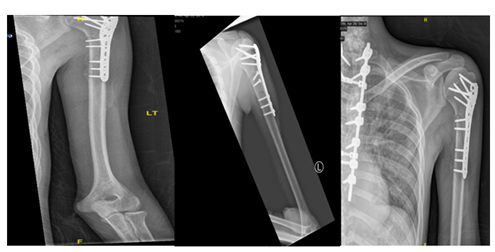

A 26-year-old male, soldier, involved in road traffic accident on 27th of August 2019 in the southern region of Saudi Arabia. The patient was transferred to the military hospital in the south and they stabilized him there and then transferred to our hospital on 29th of August 2019. The patient had multiple injuries: T3–T4 spinal fracture (Figure 1), left proximal humerus fracture (Figure 2), 8th & 9th rib fractures with multiple lacerations. He underwent for left open reduction and internal fixation of the proximal humerus by using Proximal Humerus Internal Locking System "PHILOS" plating on 03-Sep-2019 (Figure 3A & 3B). Also, the patient underwent spinal fixation for the fracture from T1 to T8on 05-Sep-2019 (Figure 3C). One month postoperatively, he started to have left big toe gangrene and vascular surgery was consulted. They recommended doing CT angiogram of the aortic arch and echocardiogram. CT showed that left pedicular screw of T6 and T8 appear lateral to the pedicle and the tip of the screws abutting the medial wall of the descending thoracic aorta at the posterior mediastinum but there is no obvious surrounding active haematoma or aortic thrombosis (Figure 4A & 4B). Pre-operative assessment and measurement were done and it was showed: Whole length supposed to be covered: 10cm, Proximal landing zone on the sagittal view: 2.67cm, Distal landing zone on the sagittal view: 1.83cm, Proximal axial: 2.14cm x 2.11cm, and distal axial: 1.92cm x 1.78cm.

Figure 2 X-ray of left shoulder showed displaced proximal humerus fracture.

Figure 3 Anteroposterior (AP) & lateral views of left humerus, post open reduction and internal fixation by PHILOS plate (05.Sep .2019) [A&B ], with posterior spinal instrumentation from T1 -T7 [C].